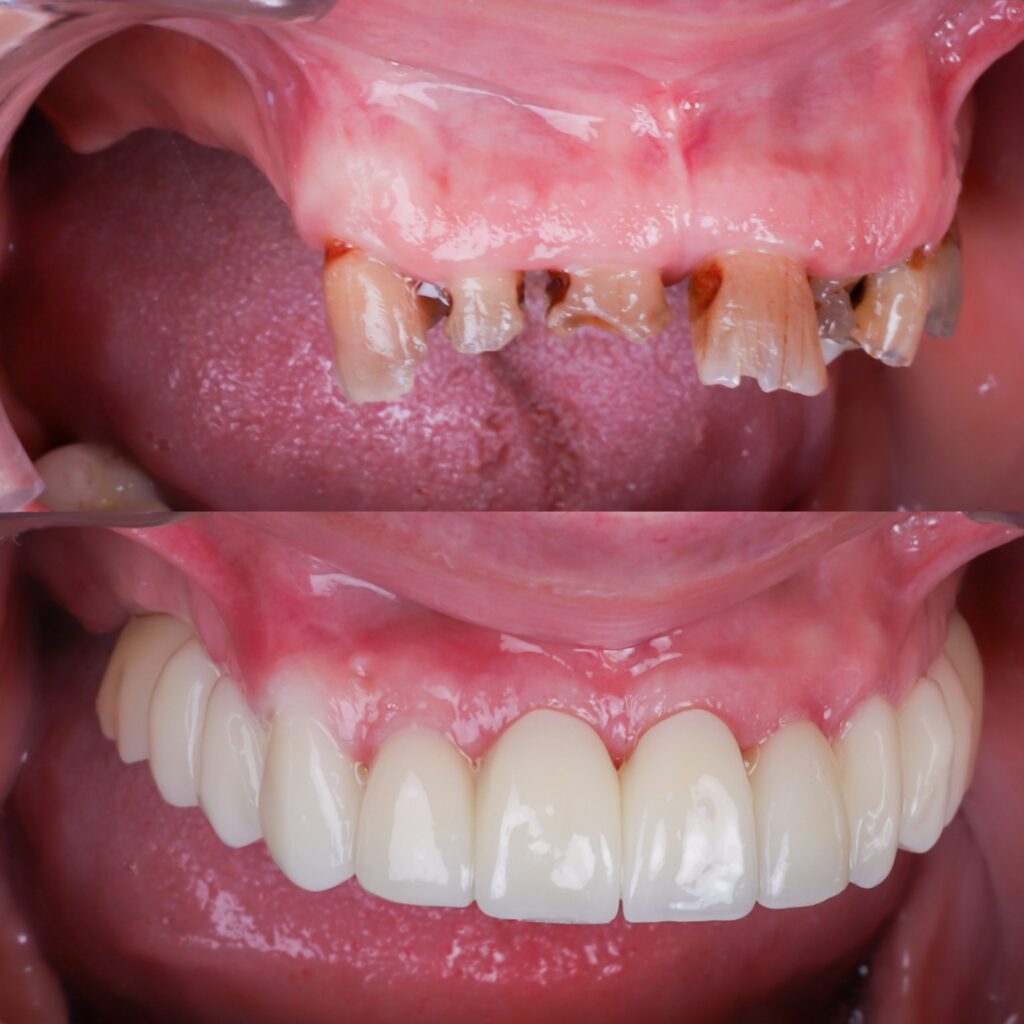

Como hemos hablado en varios post anteriores, un implante dental es una solución fija para reemplazar un diente perdido. Un implante cementado significa que la corona cerámica (el diente visible) está permanentemente unida al pilar del implante con cemento dental. Esto crea una apariencia natural y continua (sin agujeros visibles de tornillo) y una […]